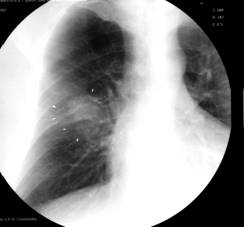

3. Tumori maligne secundare (metastaze)

Fig. 24 – Metastaze pulmonare (opacitati nodulare si macronodulare multiple, diseminate pe ambele arii pulmonare, omogene, de intensitate medie, imprecis delimitate)

Din punct de vedere radiologic intalnim 3 forme:

- opacitati rotunde unice (metastaze solitare) situate in bazele pulmonilor;

- opacitati micronodulare pe toata aria pulmonara, ce apar in diseminarile hematogene;

- limfangita carcinomatoasa, caracterizata prin edem interstitial cu trabeculatii hilifuge si linii Kerley.